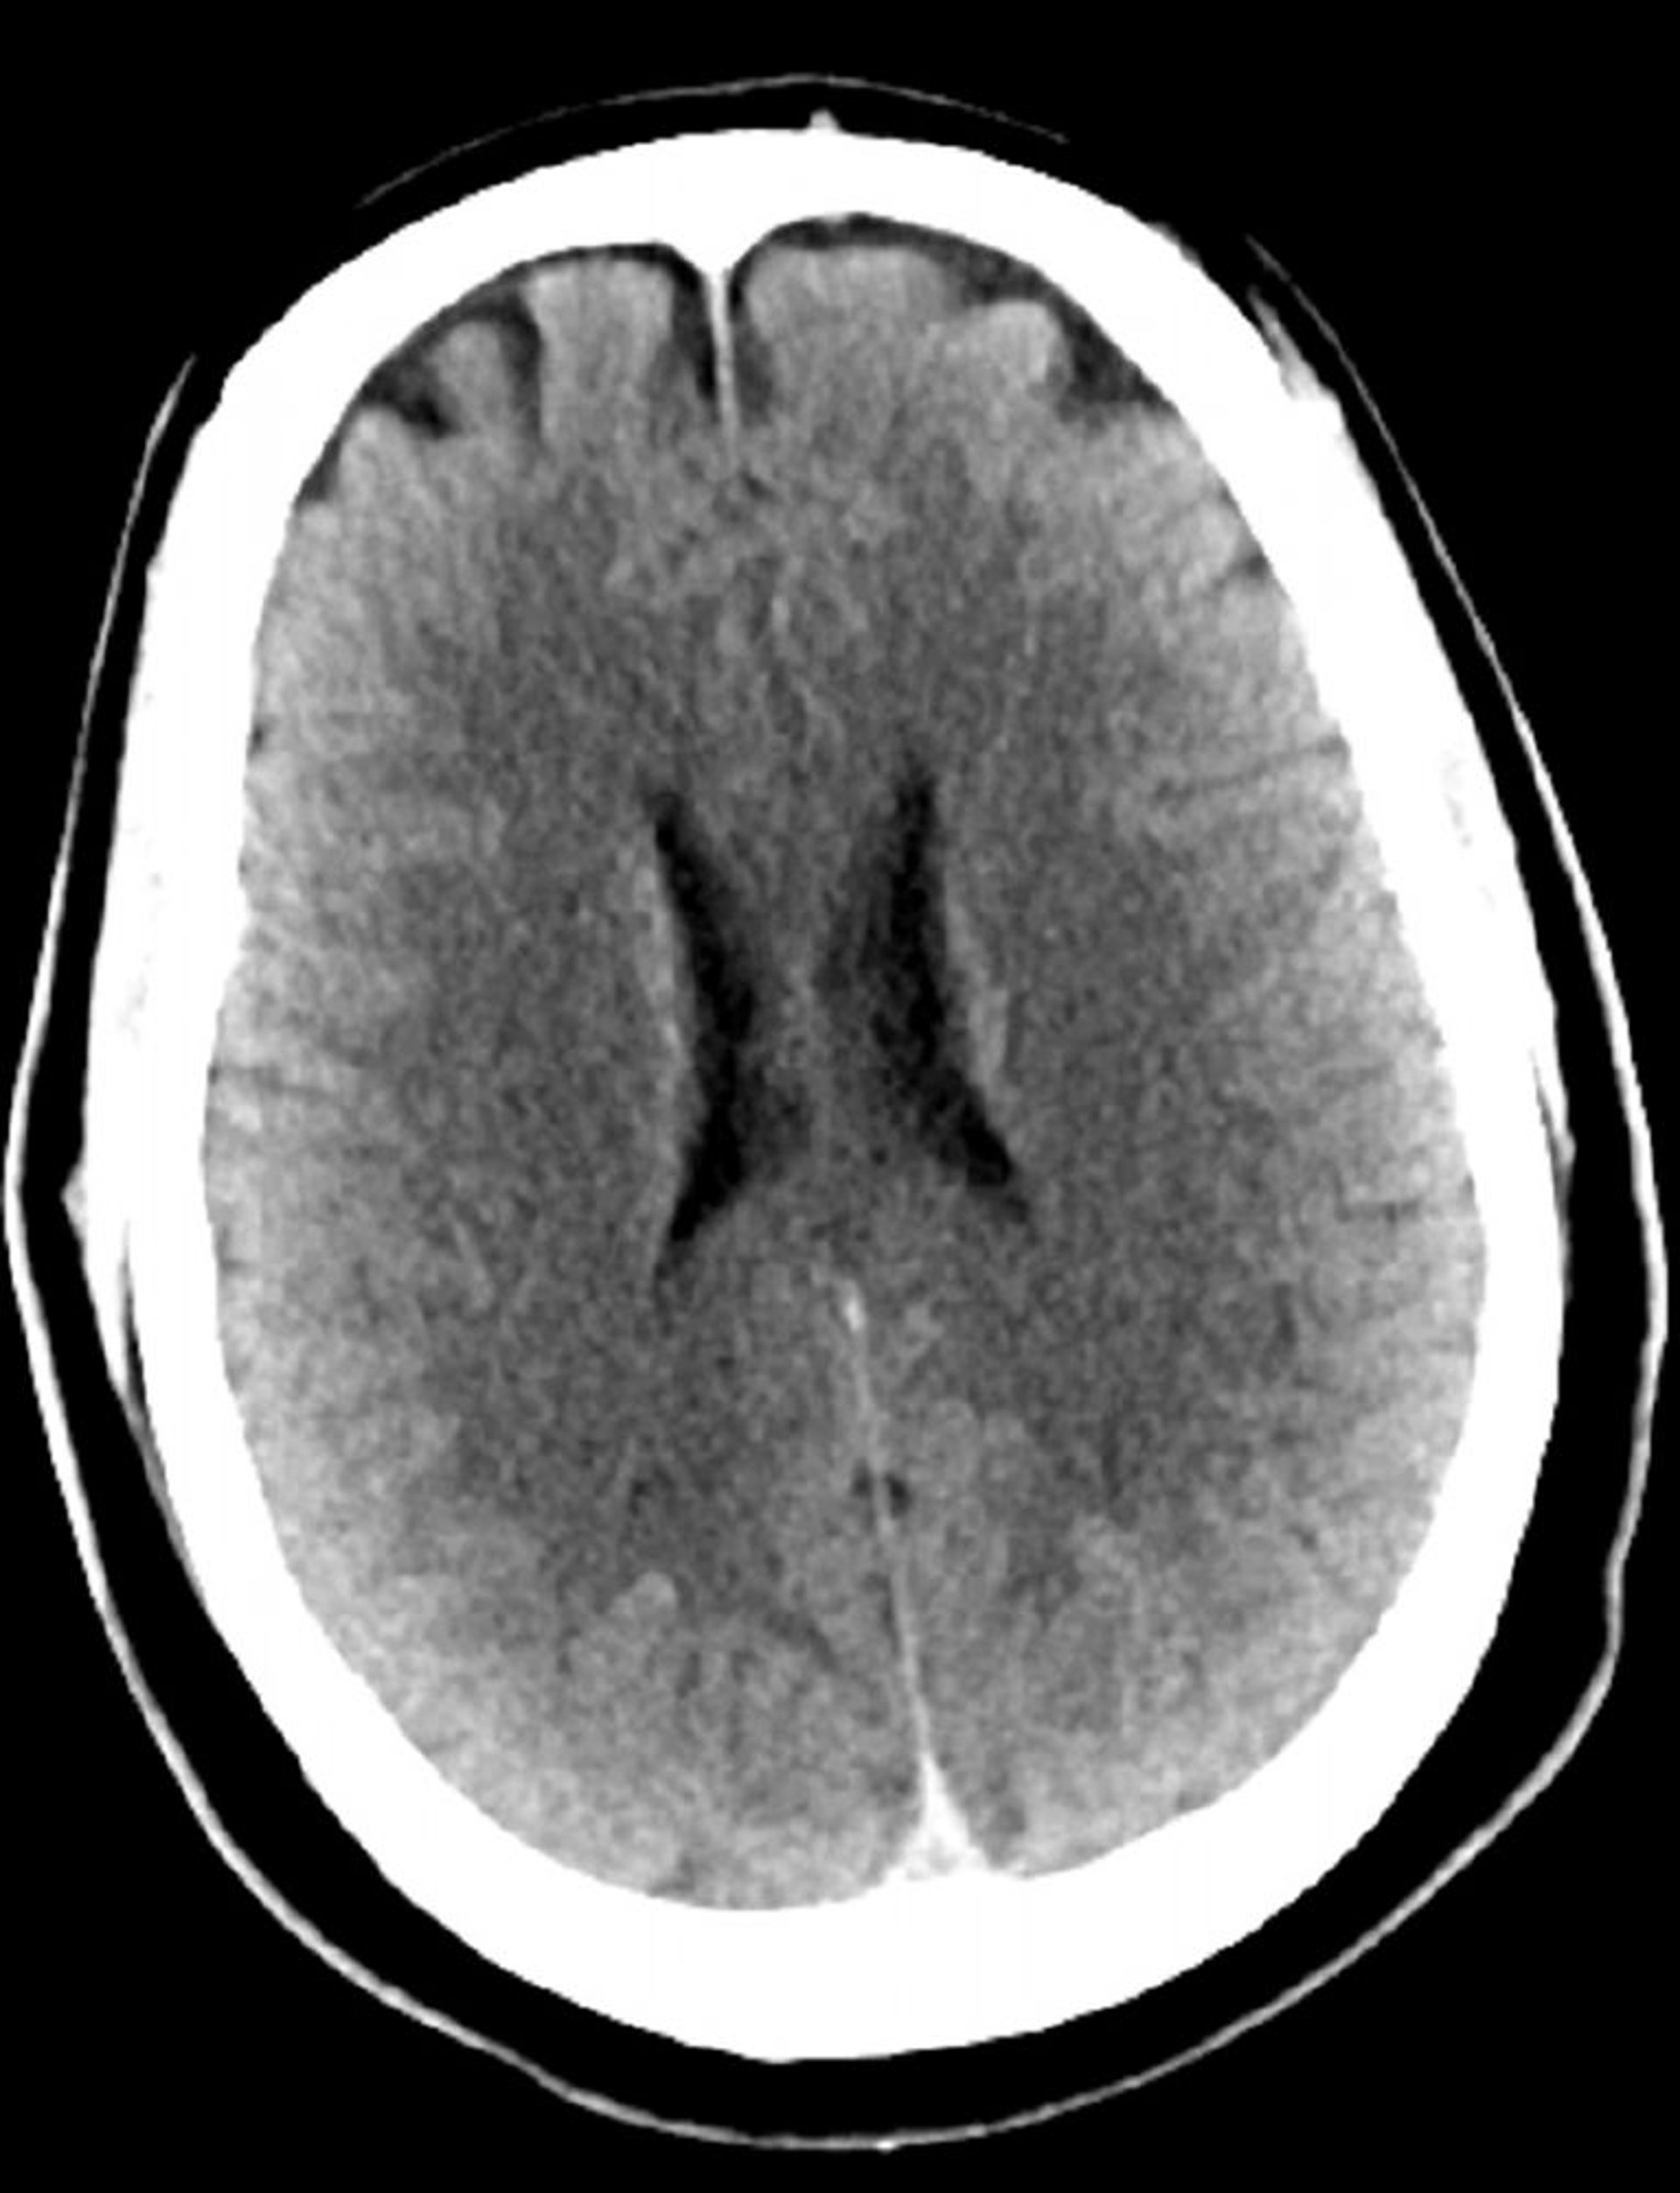

正常な頭部CT(成人,30歳)―スライド3

これは30歳の若年成人の正常な頭部CT画像である。脳実質の内外に髄液や出血はみられない。白質と灰白質の区別は維持されている。脳室の大きさと脳溝のパターンは正常である。